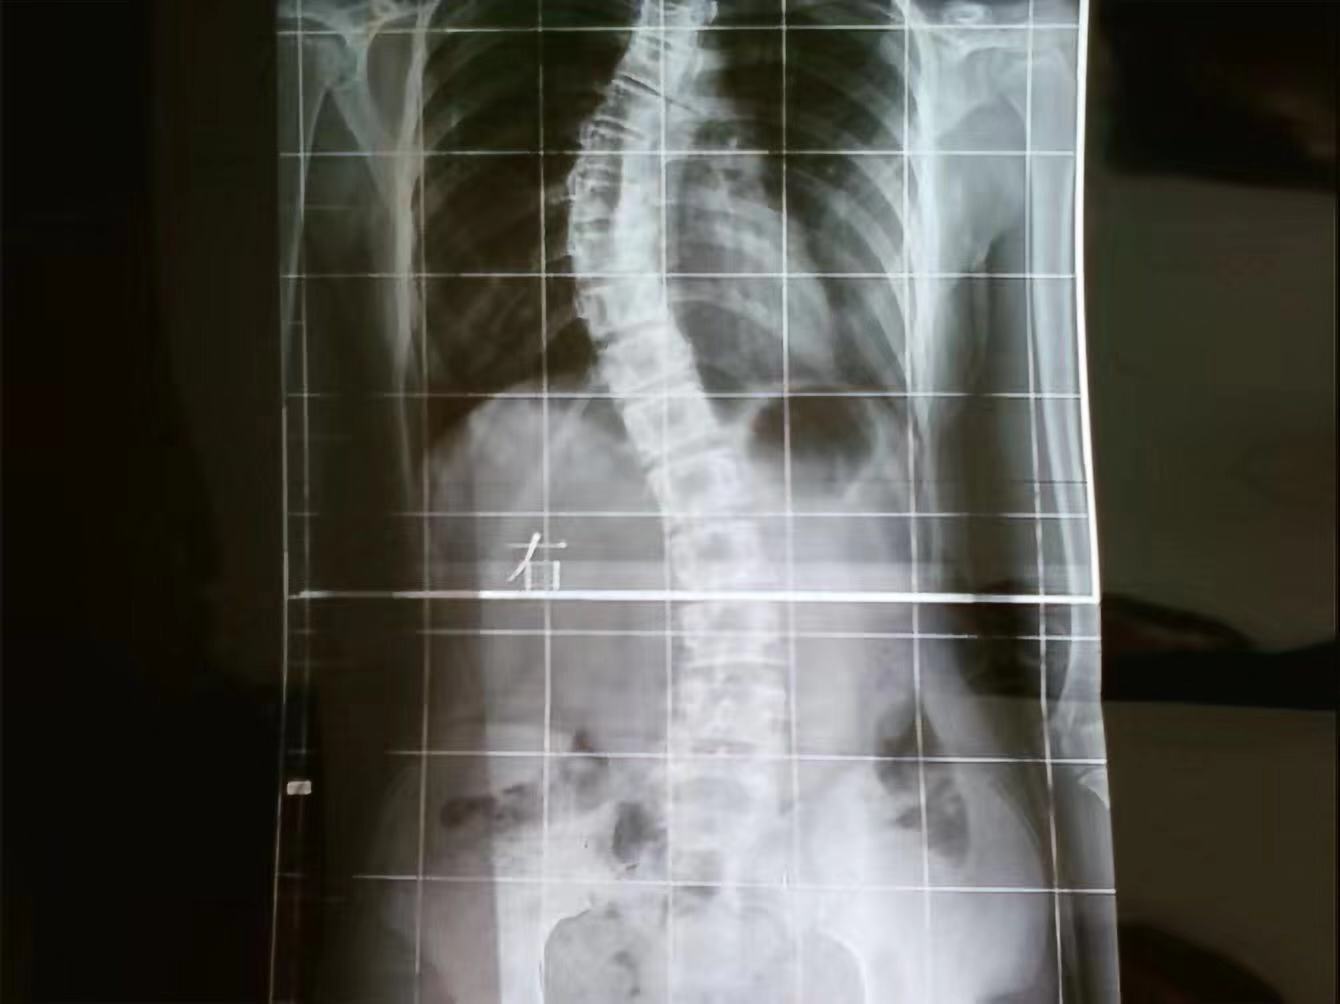

我是爱漂亮的24岁女孩。2009年,我14岁那年,同学发现我后背隆起,家里长辈也不清楚怎么回事,于是带我去了县里的医院,当时的医生也并不完全明白我的疾病,建议我去大医院检查。

经过检查确诊为“脊柱侧弯”。医生告诉我其中的利害关系,并且告诉我大概需要10多万的手术费。当时觉得天都要塌下来了。面对高昂的手术费,和手术的风险,妈妈每天发愁的吃不香睡不好,因为我是单亲家庭,对此疾病更是惊恐万分。

脊柱侧弯术前

偶然的机会,我上网咨询,在众多的脊柱外科医生里,我选择了在国际上都非常有学术地位的陶惠人教授,咨询了陶惠人教授后,我心里有了治愈疾病的一线希望。第二天我和妈妈出发去了西京医院。陶教授仔细分析了我的情况后,建议我做微创的“胸腔镜下矫正手术”。教授的答复让我如沐春风,原来手术可以让我恢复健康,可以让我像正常姑娘一样去穿漂亮的衣服,心里真的特别开心。